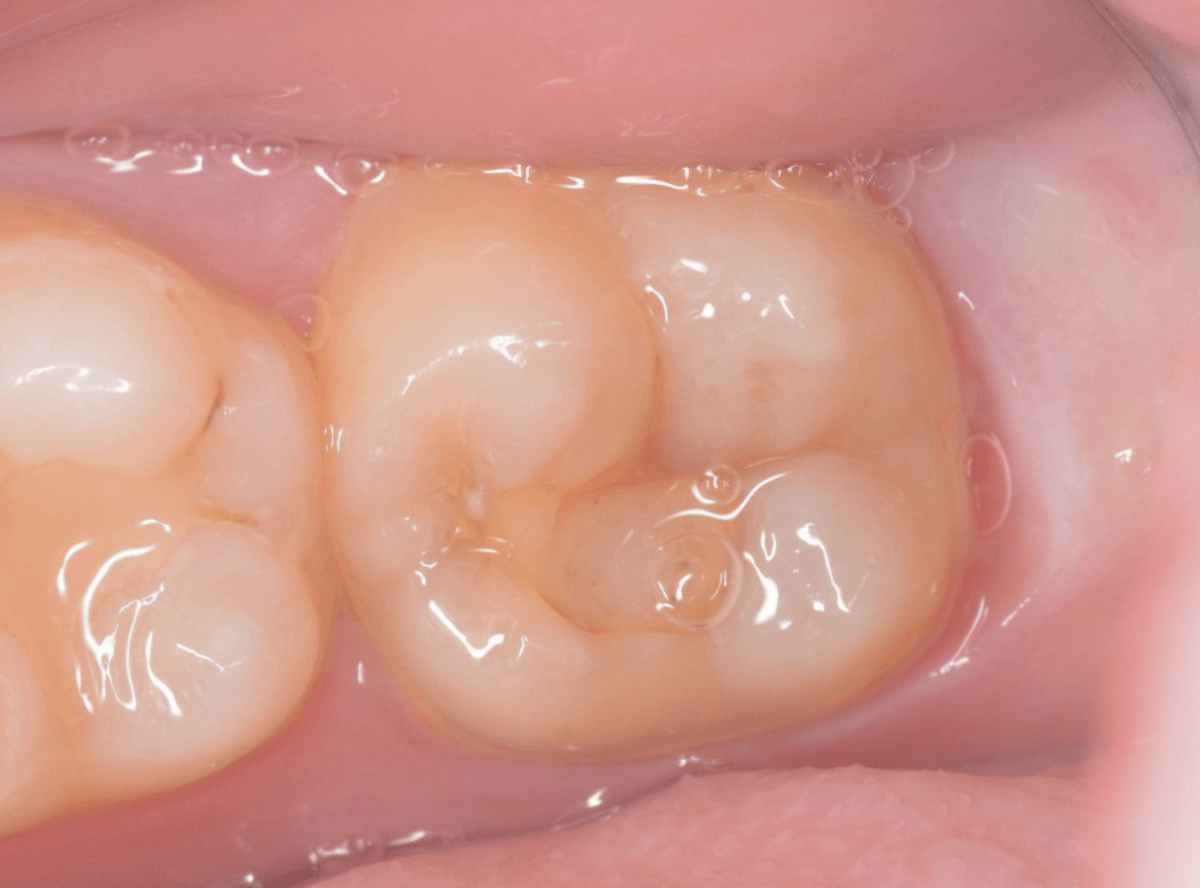

こちらは、下の奥歯の写真です。

特に症状の訴えはありませんでしたが、

歯を観察した瞬間、「虫歯がありそうだな」と思われるような所見です。

私の目には大体このように映っています。

レントゲン写真です。

私が虫歯っぽいと思っていた部分よりも、むしろ手前の部分に大きな虫歯がありました。

もう神経に触りそうな大きな虫歯です。

これだけの虫歯であれば、通常であれば、歯がしみたり、食事中に痛みがあったり何らかの症状があるのですが、無症状のこともあります。